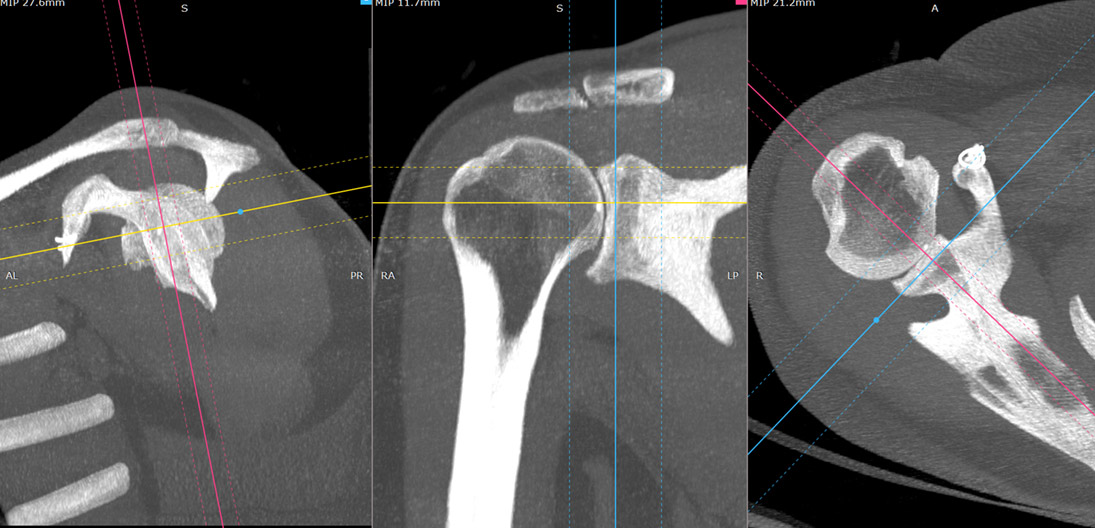

Introducerea tehnicii de achiziție spirală, care a permis achiziția continuă și rapidă a unui volum de date uriaș, cu posibilitatea de reconstrucție ulterioară în orice plan, nu doar cel transversal, precum și cu posibilitatea de reconstrucții tridimensionale spectaculoase. Inițial, achiziția se făcea doar în modul secvențial: după o rotație de 360 de grade a tubului, masa cu pacientul avansa în interiorulul aparatului cu grosimea unui slice (de obicei 10mm) și se făcea o noua achiziție. Acest mod este mai lent și nu permite reconstrucții în alt plan la fel de ușor ca achiziția spirală, la care tubul se învârte continuu, iar masa se mișca și ea în același timp. În prezent, achiziția secvențială se mai utilizează de rutină numai la examinarea cerebrală.

Creșterea vitezei de achiziție a imaginilor, în prezent putem obține imaginea statică a inimii (întreaga inima văzută într-o singură bătaie de inimă). Se obțin secvențe din ce în ce mai fine, slice-ri cu grosime de 0.5-1mm și rezoluții geometrice din ce în ce mai mari.

Evolutia calculatoarele permite in prezent prelucrari complexe ale imaginii achizitionate, pe console speciale, fara a mai fi nevoie de prezenta pacientului. Astfel, imaginile sursa sub forma unui volum impresionant de date ce acopera o anumita regiune a corpului pot fi prelucrate in multiple moduri: